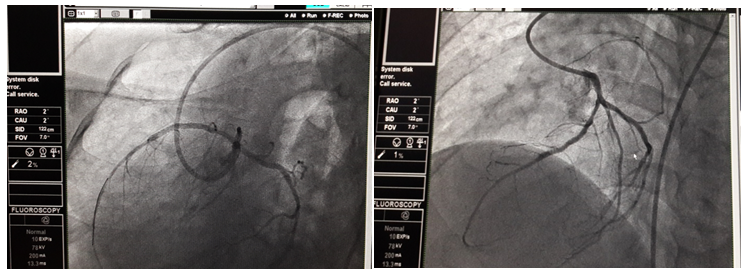

52 years male who is a chronic smoker with systemic hypertension was referred to our center for management of acute ST elevation anterior wall MI. He was managed in outside cardiac center with thrombolysis with streptokinase. Patient gives the past history of thoracotomy for repair of diaphragmatic hernia. On clinical examination, vitals were stable. Cardiovascular system (CVS) examination: Apex localized to the right 5th intercostal space. There was decreased air entry over the left inter/infrascapular and axillary lung zones. Chest X-ray was suggestive of elevation of left dome of diaphragm with fundus air shadow with dextrocardia (apex pointed to right side with right sided aortic knuckle) (Figure 1). Electrocardiogram was suggestive of dextrocardia (decreasing voltages from V1-V6) as shown below in Figure 2. Echocardiography showed dextrocardia with mild LV systolic dysfunction (LVEF-40%) with regional wall motion abnormality (RWMA) along LAD territory. Troponin I was positive (0.1ng/ml) and CPK-MB was 80IU/L. Coronary angiography was done with Judkins left and right (JL and JR) 3.5×6F diagnostic catheter. It revealed single vessel disease over mid-LAD (90% stenosis) as shown in Figure 3. Subsequently, left coronary artery was hooked with EBU 3.5×6F catheter. BMW wire was used to cross the lesion followed by multiple predilatations with 2×10 mm balloon. Successful PCI was done with deployment of NOVUS drug eluting stent (Sirolimus eluting stent) 2.75×32mm at 14atm.pressure as illustrated in Figure 4. 150 ml of contrast (non-ionic, iso-osmolar Iohexol) was used during the procedure. TIMI III flow was achieved. During shifting of the patient to the coronary care unit (CCU), patient had accelerated hypertension with increasing shortness of breath and desaturation(Sp02<90%) which was suggestive of acute pulmonary edema. The patient responded with diuretics, nitroglycerin infusion, morphine and high flow oxygen support within hours. Patient was discharged on fourth day in stable condition.

Figure 4: Coronary angioplasty of mid-LAD with deployment of NOVUS (SES) 2.75×32mm stent.